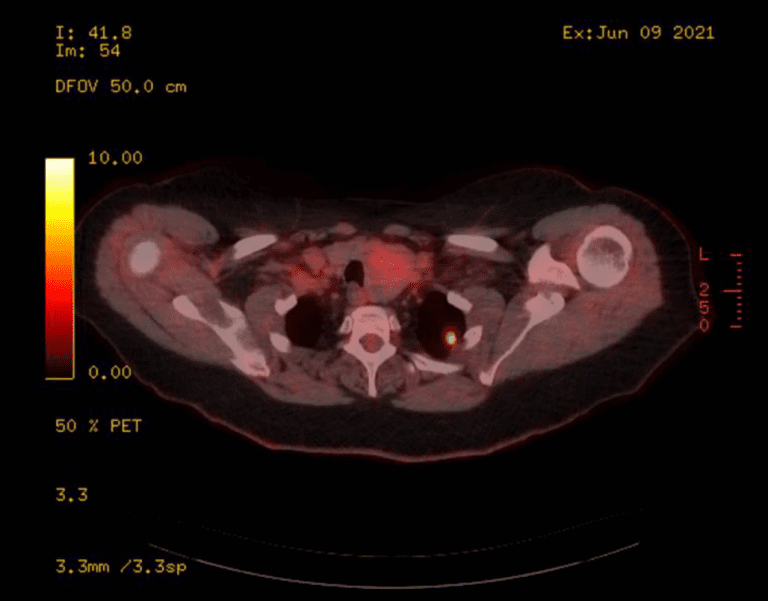

In June 2021 Mrs B remained well however a PET/CT scan showed a growing, avid left upper lobe lesion (SUV 9.7) but no signs of progression elsewhere.

Figure 1 : PETCT scan showed the growing, avid left upper lobe lesion (SUV 9.7)

The images were reviewed in the local lung MDM and the peripheral left upper lobe nodule was felt to represent oligoprogressive disease. For this reason, I considered her potentially eligible for simple SABR to the lung nodule to maximise her disease control. On discussion she was keen to go ahead with treatment.